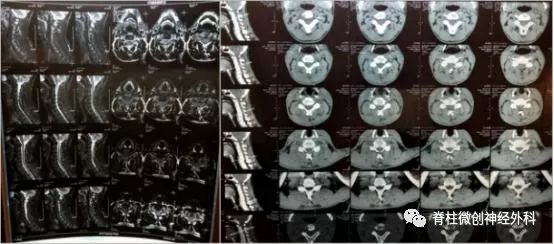

影像资料

患者年纪并不大,从原则上来说是不应该出现退变的。从影像学检查来看,患者并没有出现颈椎生理曲度和椎间盘的异常;患者也没有出现颈椎管狭窄,脊髓没有受到影响。颈椎并没有出现明显的不健康,所以可能是颈部肌肉劳损或者其他疾病。